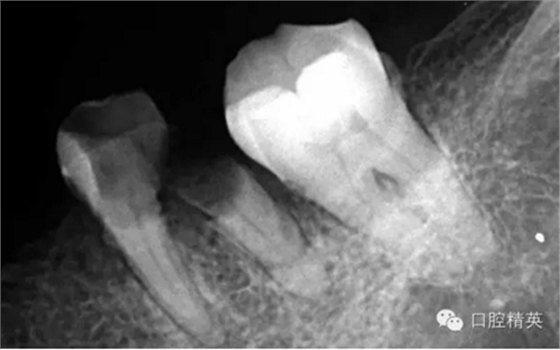

這個病例是我準備分根的病例,保留近中根,曾在外院做過干尸長達數(shù)十年。8號挫疏通時近舌根堵,近頰未找到。在這個病例中首先要知道是為什么根管難以疏通,首先是長時間的干尸,和患者年紀較大根管逐漸變窄,根管道路可能會出現(xiàn)堵塞,在這張病例中我能知道的是稍有不慎就會形成臺階,從而導致根管堵塞加重,更加難以疏通。

近舌8號k挫疏通,根尖部彎曲,我花費時間2小時疏通。我個人覺得根管能否被疏通,第一個重要因素是時間,因為作為牙體牙髓的醫(yī)生,首先就是需要的就是耐心。我個人覺得耐心是非常重要,因為很多根管被疏通時,都是我們快要放棄的時候。所以我每次都會安慰自己快好了,快好了,就差一點點,在堅持一會兒就好了。可以說沒有耐心,想做好牙體牙髓,我個人覺得很難很難。第二個就是手法,不知道大家啟用挫是什么挫,一般我個人認為,最好從8號開始疏通,這樣不容易在狹窄的根管內(nèi)形成臺階(如果有條件的可以從6號開始)。